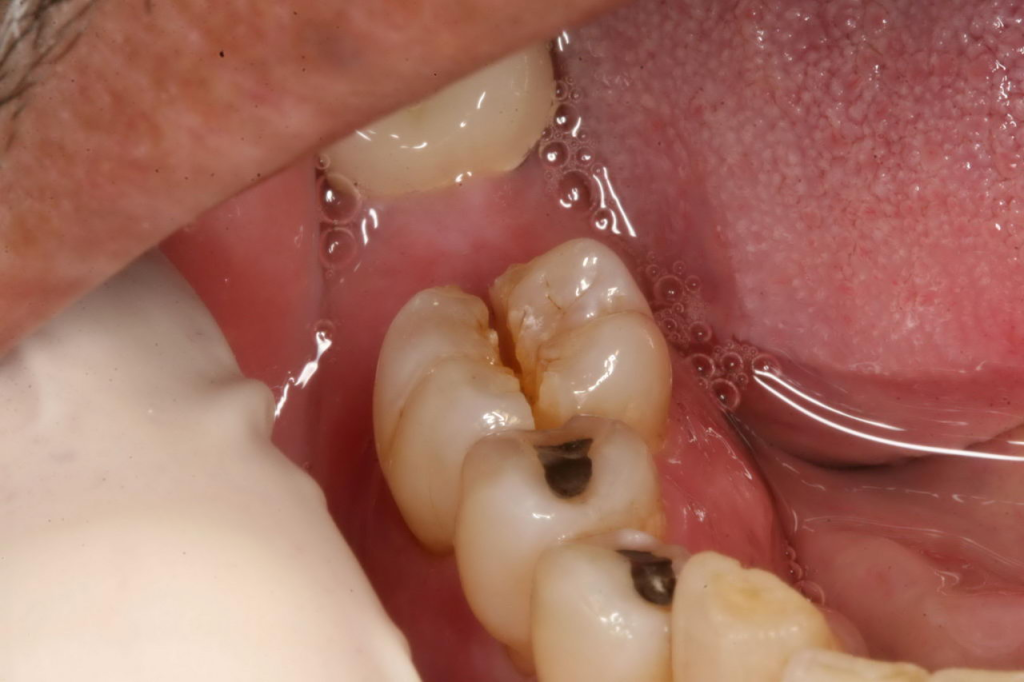

Diş çekimleri, diş eti ameliyatları, gömük diş operasyonları gibi ağız içi operasyonlardan sonra öncelikle o günü dinlenerek geçirmeyi unutmayın, aşırı aktivite, stresli işler ve spo yapmaktan kaçının. Operasyon ve diş çekimi sonrasında yara bölgesine konulan tamponu 30 dakika boyunca baskı uygulayacak şekilde ısırmanız gerekmektedir. 30 dakika sonra atabilirsiniz, yerine tekrar tampon koymanıza eğer doktor tavsiye etmemişse çoğu zaman gerek yoktur.

Kıymetli Hastamız! Kliniğimizde cerrahi işlemler dışında diş beyazlatma, porselen kaplama, gülüş tasarımı, tedavi (diş dolgusu, kanal tedavisi), hareketli (total ve parsiyel protezler), hibrid (implantüstü) ve sabit protezler (porselen, zirkon, lamina) ile temel dişeti hastalığı tedavilerini (diş taşı temizliği, küretaj) de yapmaktayız. Sağlıklı günler dileğiyle!